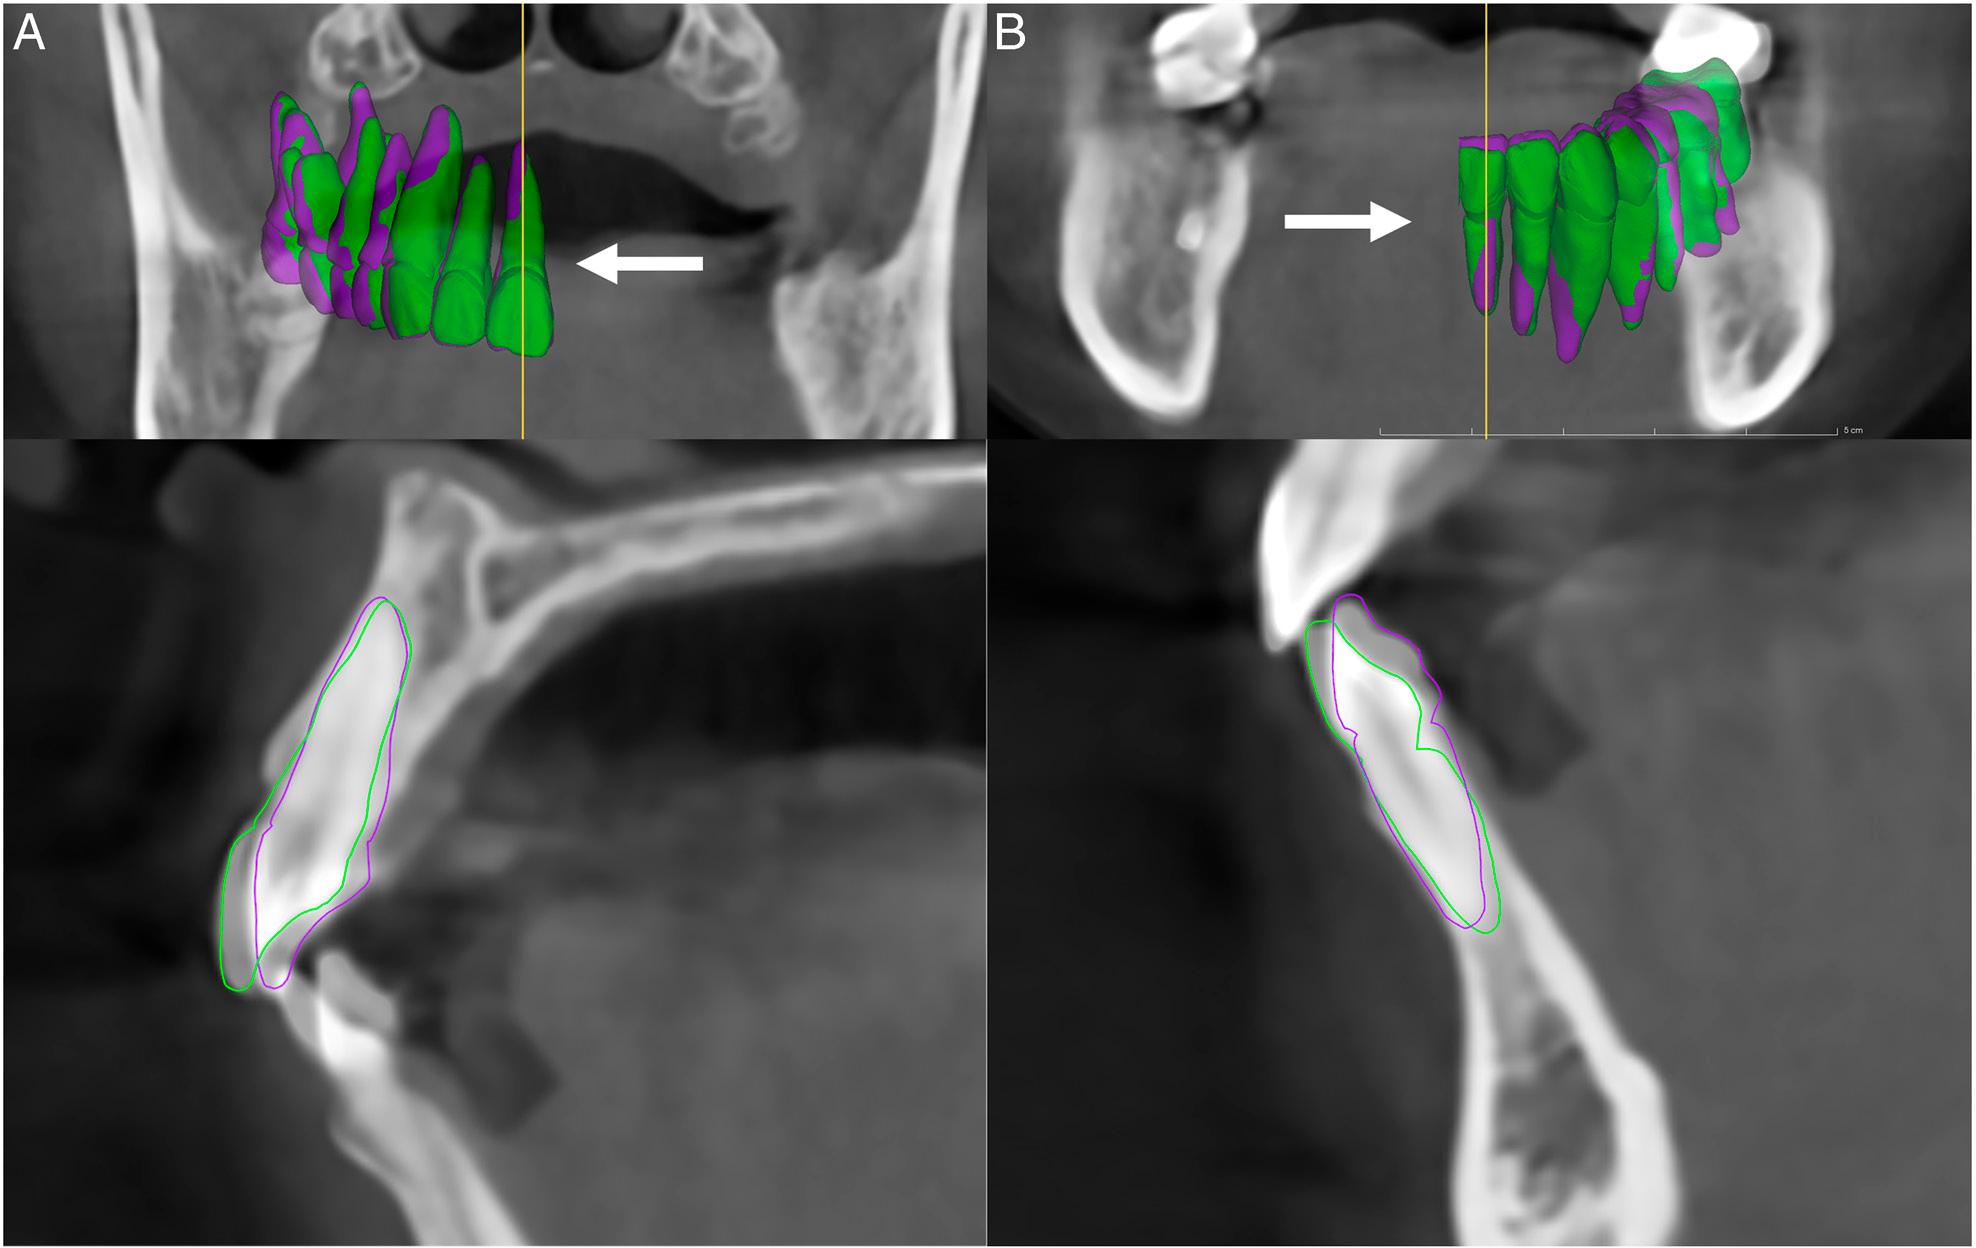

Figure 3.